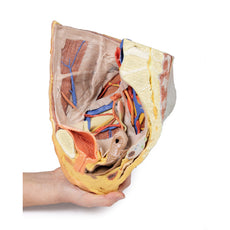

This 3D model represents one of the largest and most complex in the series, consisting of a partial torso from the diaphragm to the proximal thigh with a complete abdominal cavity preserving varying levels of dissection. This 3D model also records the rare, simultaneous occurrence of indirect and direct inguinal hernias allowing for a consideration of the anatomical underpinnings for both conditions. Given the scale of the dissection this 3D model description is divided into discrete parts based on views and regions.

The epigastric and hypochondriac regions

Within the abdomen, the anterior abdominal wall, greater omentum, and

much of the gastrointestinal tract has been removed alongside the parietal peritoneum over the posterior

abdominal wall to expose retroperitoneal organs and structures. In the superior abdomen, the terminal portion of

the oesophagus has been retained and can be seen entering the cavity just lateral to the left lobe of the liver.

The removal of the stomach has exposed the extent of the pancreas from the head (positioned within the arc of

the duodenum) to the tail extending to the capsule of the spleen preserved in the left hypochondrium. Superior

to the pancreas, the splenic artery and common hepatic arteries can just be observed spanning across the narrow

space between the pancreas, diaphragm and liver. The splenic follows its archetypical ‘tortuous route’

towards the spleen, and strongly divides prior to reaching the hilum (and adjacent to the splenic vein). The

common hepatic can be seen dividing into the gastroduodenal (visible again as a cut vessel just inferior to the

duodenum) and giving off the right gastric artery; these vessels lie superficial relative to the hepatic portal

vein. The superior mesenteric artery and vein can be seen passing anteriorly near the head of the pancreas and

horizontal part of the duodenum, and the retained ileocolic artery can be traced to the caecum of the large

intestine in the lower right quadrant of the abdomen. The inferior mesenteric vein can be, in part, appreciated

arising from the retained superior rectal vein ascending from the undissected true pelvis and spanning across

the superficial aspect of the descending thoracic aorta.

Inferior to the liver the gallbladder can be viewed just between the right and left anatomical lobes. On the left, the passage of the renal artery and vein can be seen just deep to the pancreas, and the ureters can be observed descending from the partially exposed kidney across the superficial surface of the exposed psoas major and minor muscles.

The umbilical and lumbar regions

Most of the organs occupying the umbilical and lumbar regions of the abdomen

have been removed in order to expose structures in the posterior abdominal wall. In the midline, the descending

abdominal aorta and inferior vena cava dominate the region, with the testicular arteries and veins isolated and

traceable towards the inguinal regions. Two right lumbar arteries are visible arising from the aorta, and

despite removal of the mesenteries and most of the colon the inferior mesenteric artery can be seen giving rise

to the left colic, sigmoid and superior rectal arteries. On the right side of the specimen inferior to the

kidney, the subcostal, iliohypogastric and ilioingual nerves are exposed alongside the circumflex iliac artery.

The hypogastrium and iliac regions

In the midline, the bifurcation of the descending abdominal aorta into the

common iliacs (and subsequent division into the internal and external iliacs) can be observed deep to some of

the overlying structures (e.g., testicular vessels, ureters) noted previously. On the right side, the obturator

artery can be seen traversing from its origin towards the anterior aspect of the pelvis. The mirrored merging of

external, internal and common iliac veins into the inferior vena cava is also preserved. Within the confines of

the true pelvis the peritoneum has been retained over the region, covering the urinary bladder adjacent to the

pubic symphysis and obscuring the rectum as it descends from the sigmoid colon. In the right iliac region the

very terminal part of the ileum and caecum with appendix fill the iliac fossa, with the appendix (and

appendicular artery) visible just superficial to the testicular artery, vein and genital branch of the

genitofemoral nerve descending towards the inguinal canal. In the left region, the sigmoid colon descends across

the iliac fossa. As it approaches the anterior abdominal wall, an epiploic appendage contribution to the

indirect hernia can be observed just lateral to the retained inferior epigastric artery.